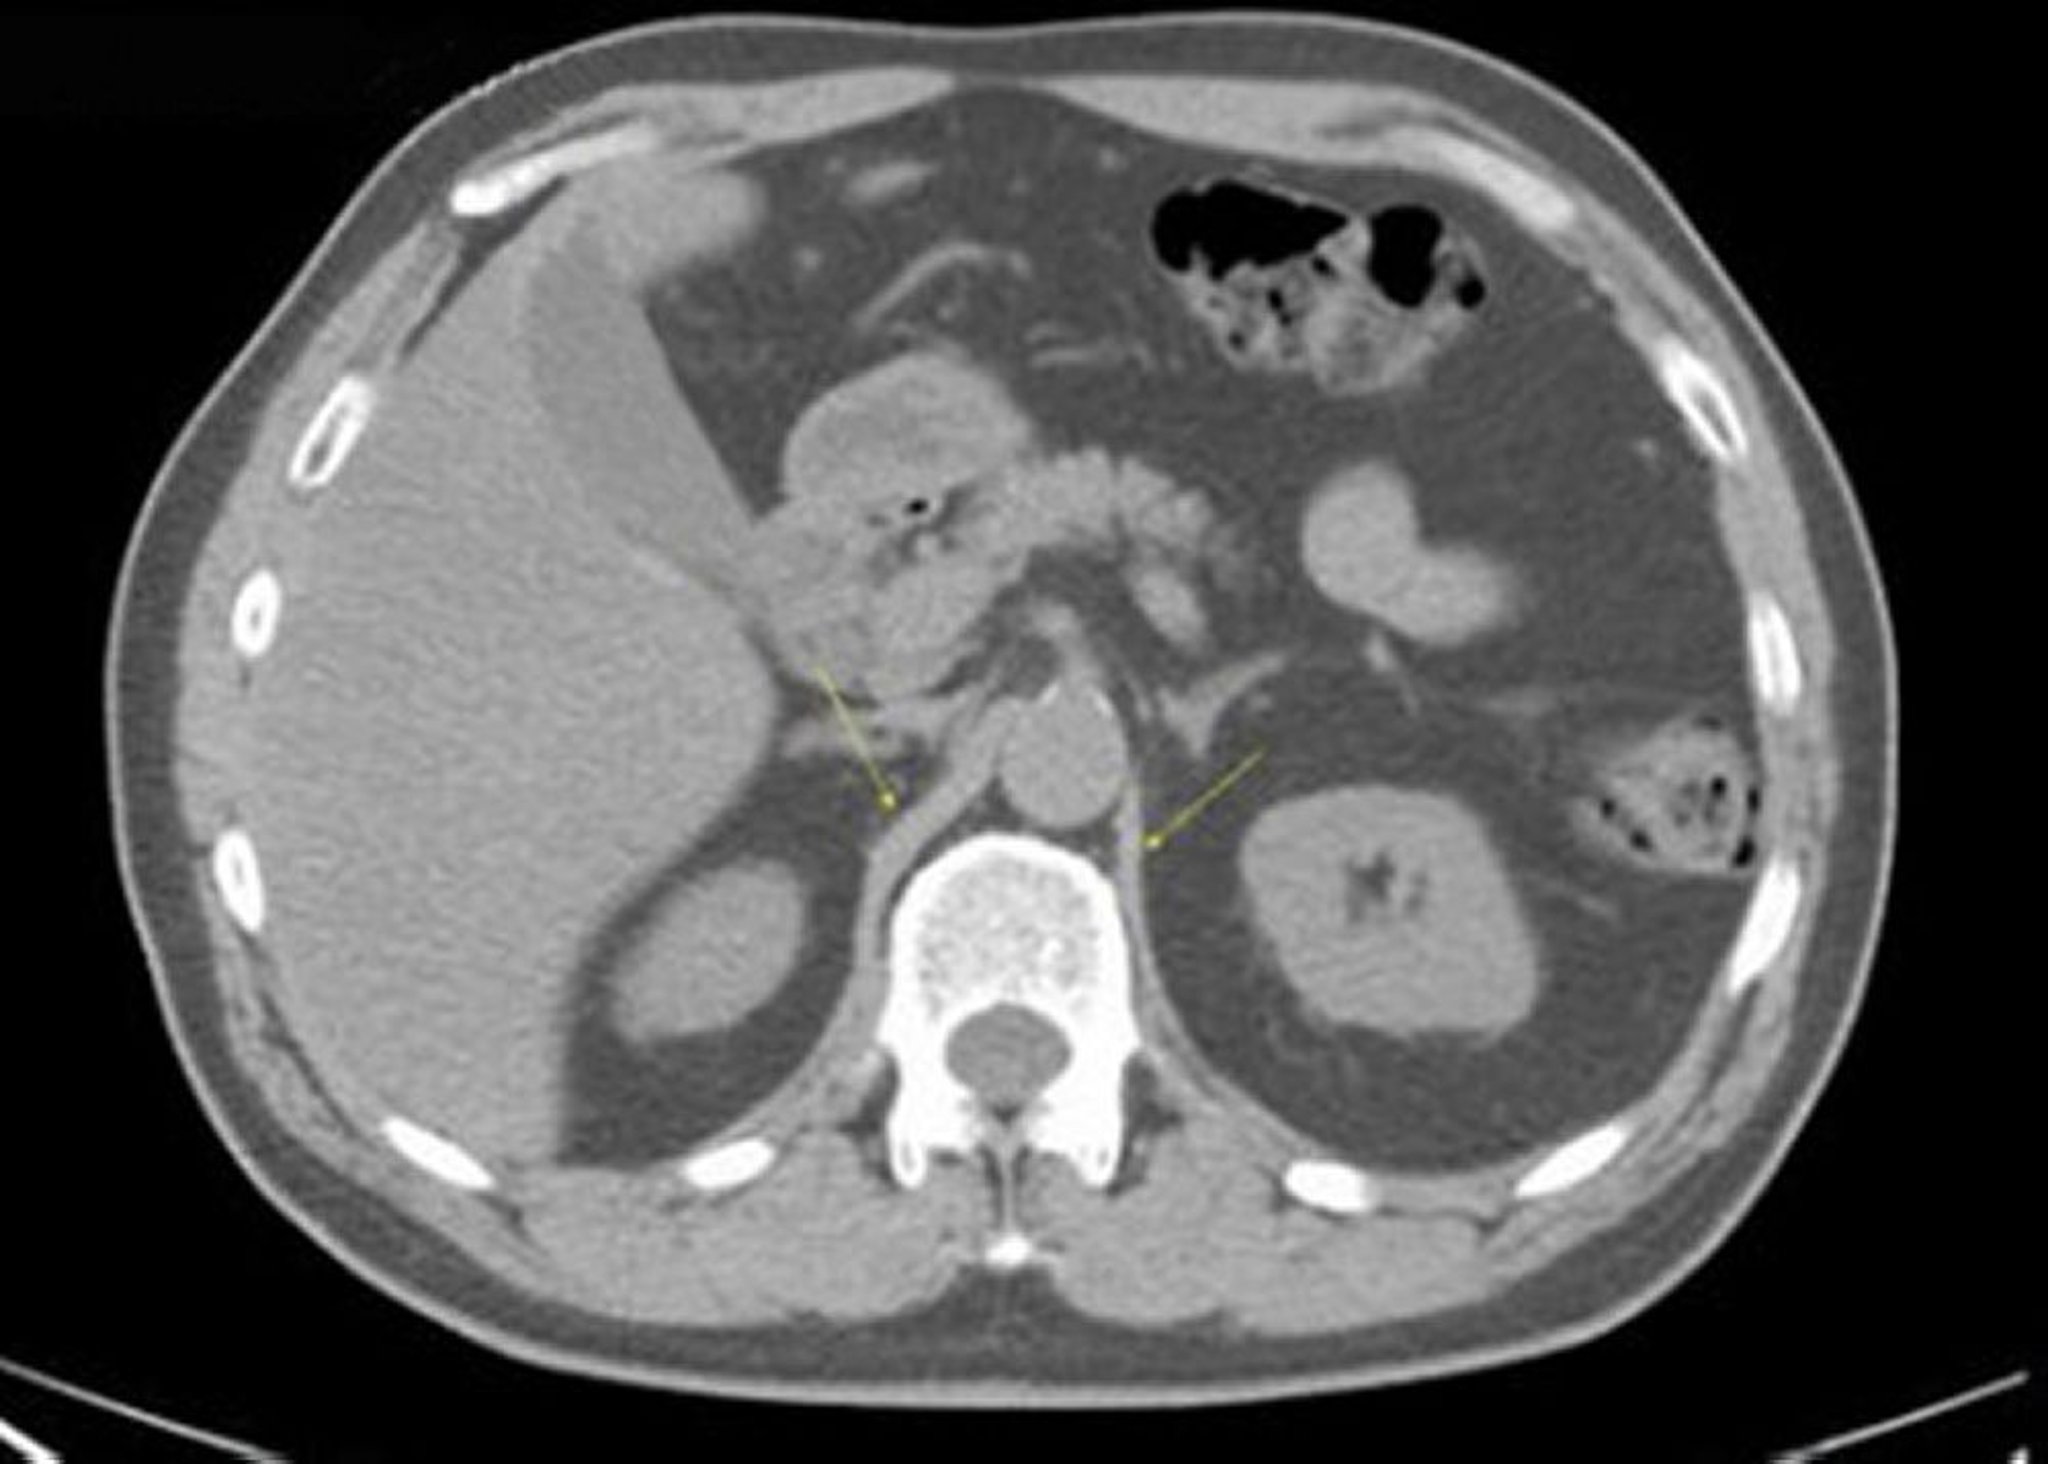

TDM sans contraste de l'abdomen et du bassin montrant une anatomie normale (diapositive 10)

Cette image montre les piliers du diaphragme (flèches).